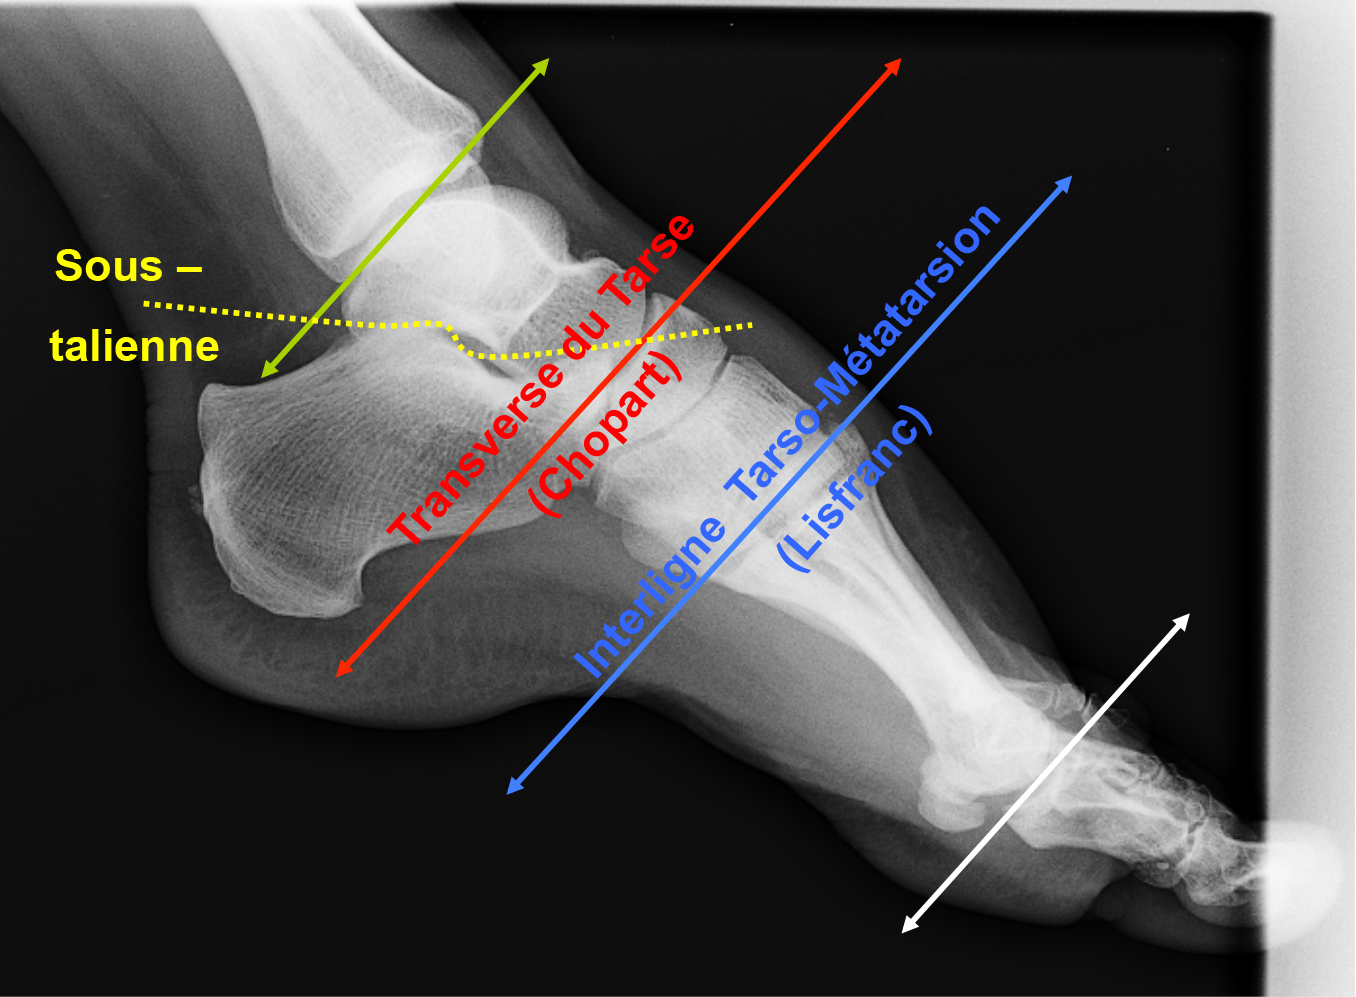

Rappel sur les articulations de la cheville et du pied.

On distingue :